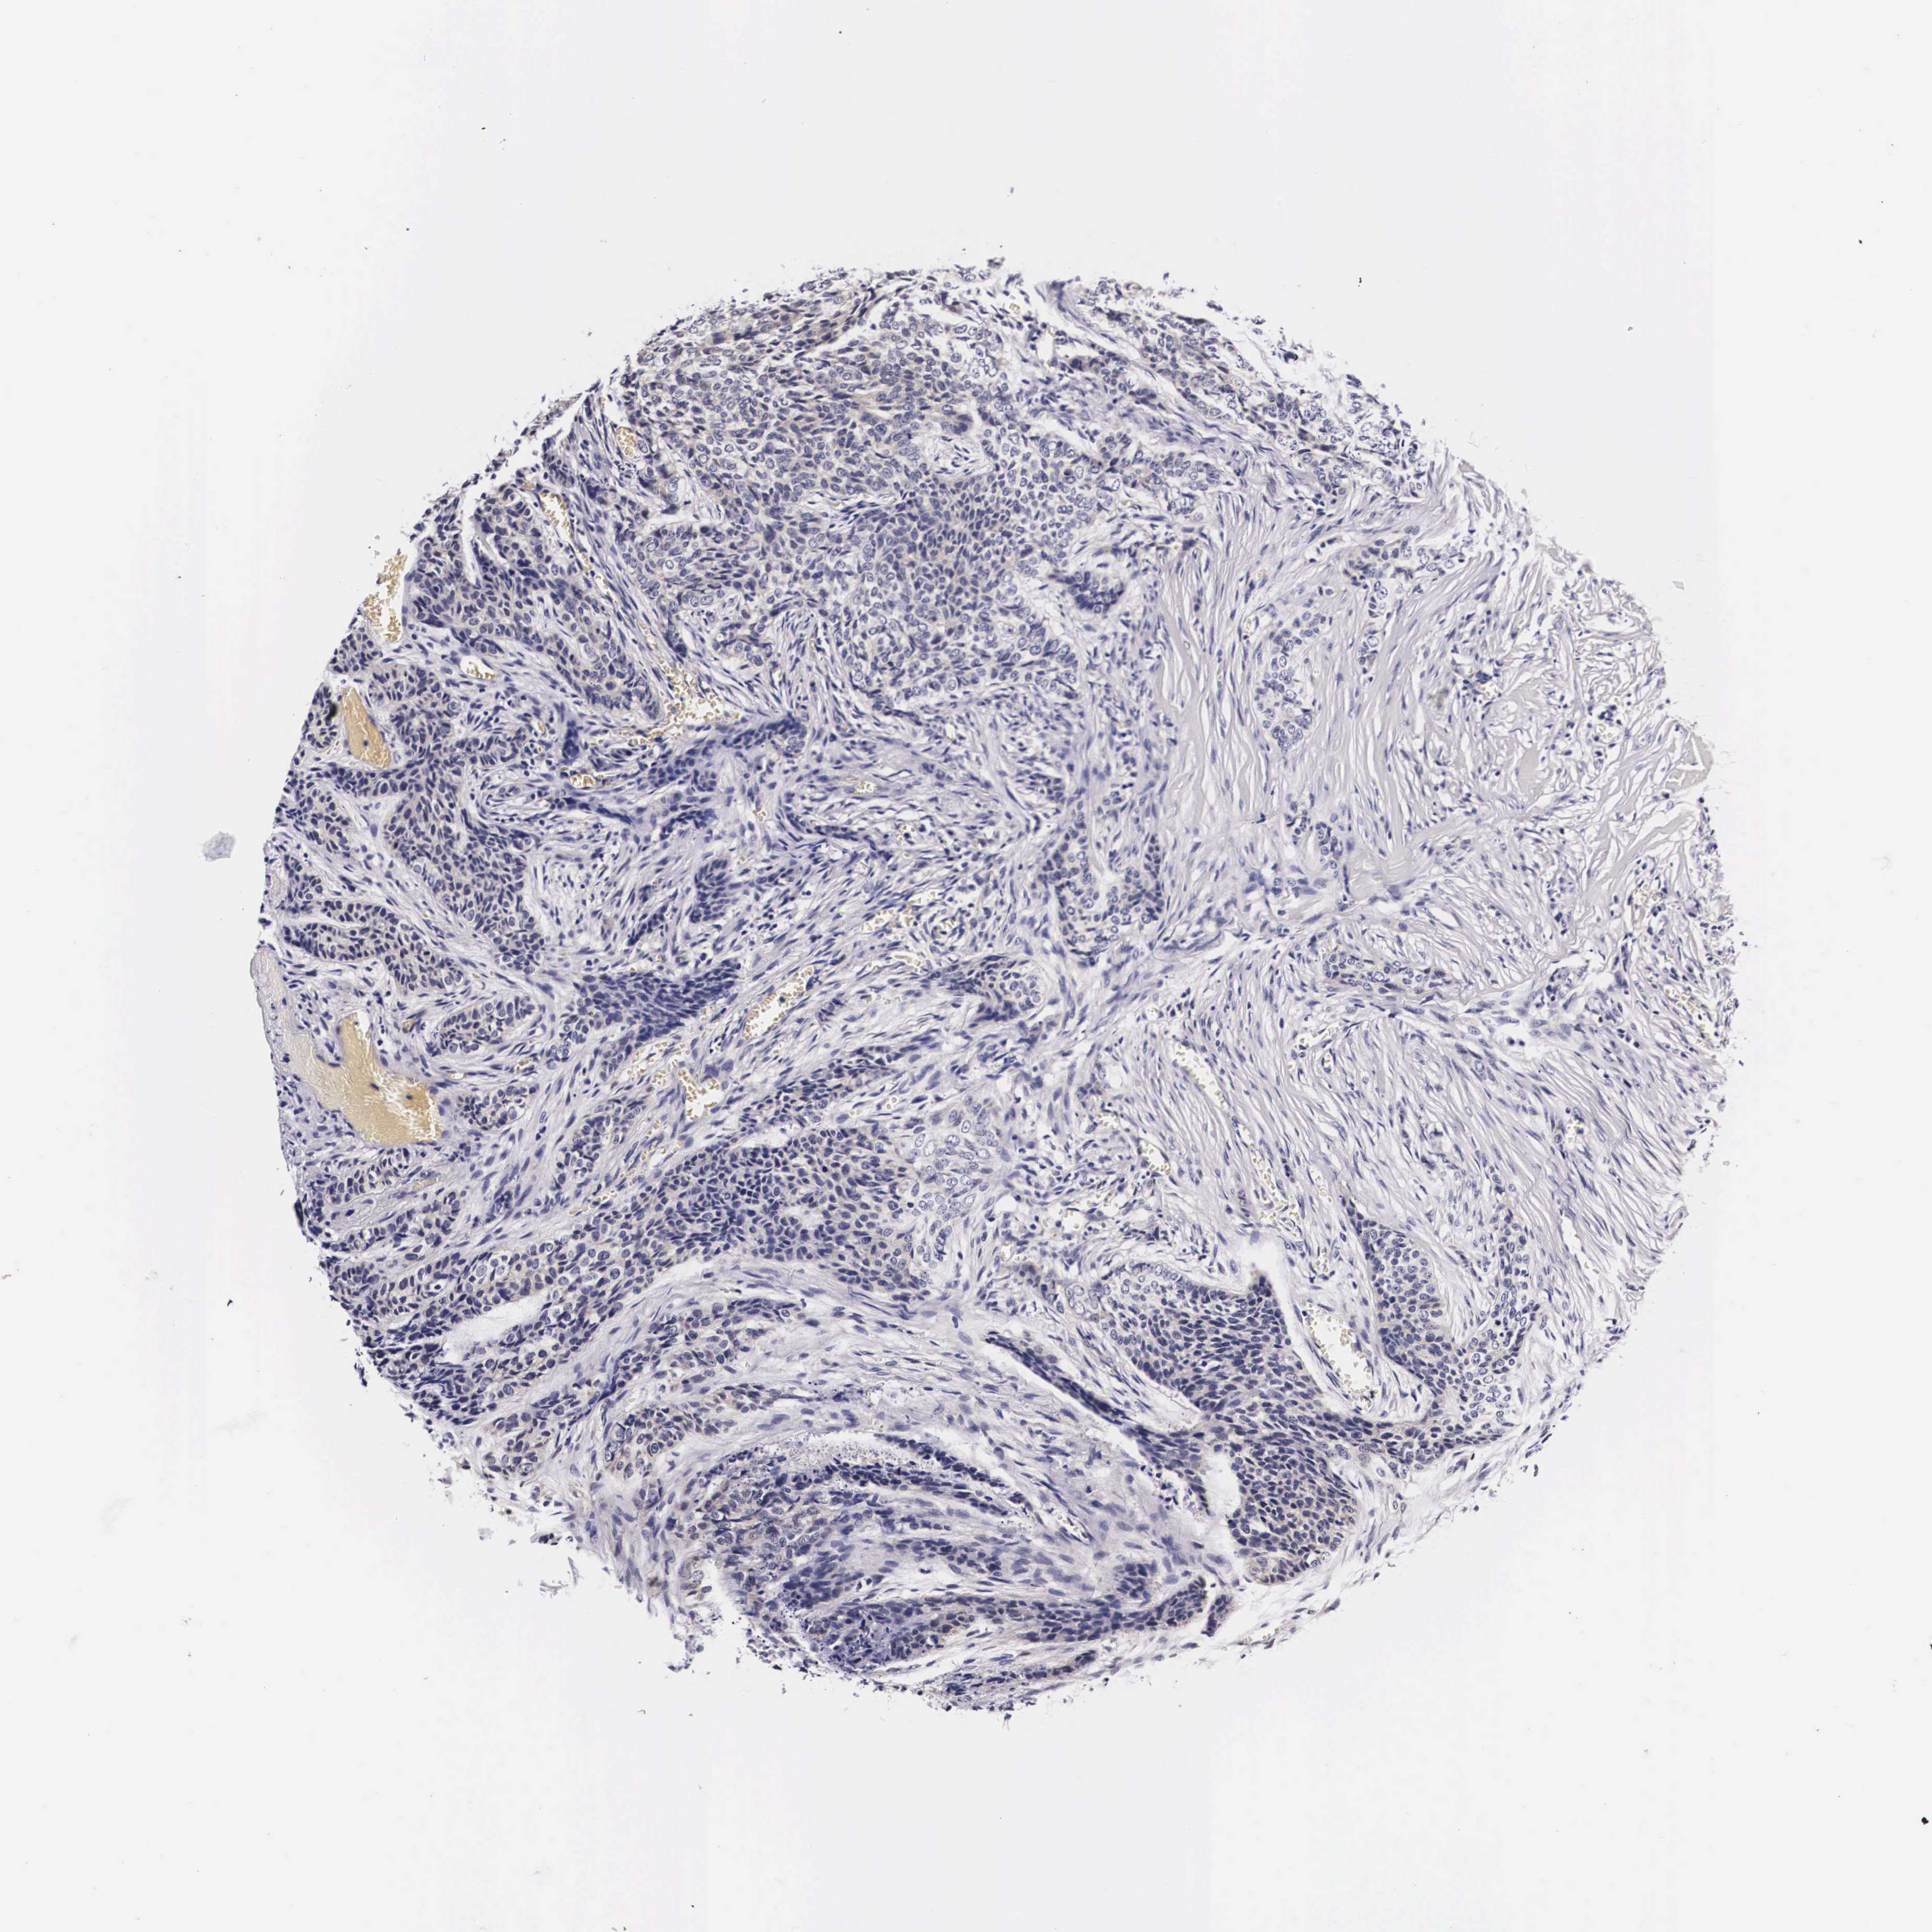

SKIN CANCER - Protein expressioni

A mouse-over function shows sample information and annotation data. Click on an image to view it in a full screen mode. Samples can be filtered based on level of antibody staining by selecting one or several of the following categories: high, medium, low and not detected. The assay and annotation is described here.

Antibody stainingi

Antibody staining in the annotated cell types in the current human tissue is reported as not detected, low, medium, or high, based on conventional immunohistochemistry profiling in selected tissues. This score is based on the combination of the staining intensity and fraction of stained cells.

Each image is clickable and will lead to virtual microscopy that enables deeper exploration of all samples and also displays staining intensity scores, fraction scores and subcellular localization as well as patient and tissue information for each sample.

Antibody HPA000647

Staining

High

Medium

Low

Not detected

Intensity

Strong

Moderate

Weak

Negative

Quantity

>75%

75%-25%

<25%

None

Location

Nuclear

Cytoplasmic/membranous

Cytoplasmic/membranous,nuclear

Squamous cell carcinoma, NOS

Basal cell carcinoma